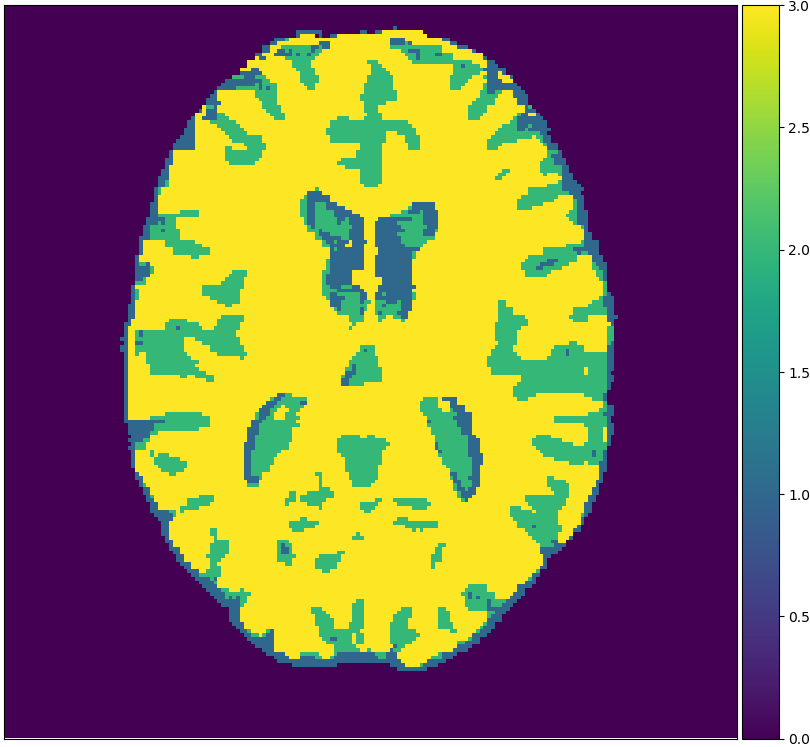

We will make use of 3 publicly available data sets: Brainweb1.5T, MRBrainS13, and IBSR. Each data set originates from one medical center. Brainweb1.5T is based on 20 realistic phantoms from Brainweb [2] and an MRI simulator (SIMRI; [3]). The simulator was set to use TE, TR and flip angle parameters of the 1.5T scanner in the Rotterdam Scan Study [9]. MRBrainS13 is a grand challenge for medical image tissue segmentation methods containing 5 scans for training [14]. The scans are 3T and have been fully manually annotated. IBSR is a classical data set of 18 patients and is automatically segmented but manually corrected [18]. Skulls are stripped off in all scans. Figure 1 visualizes examples from these sets.

Figure 2 shows examples of each segmentation method on the MRBrainS13 data set, with Brainweb1.5T as the source center. For the unsupervised models we only show boundaries between clusters, to indicate that interpretation remains a necessary step. A couple of observations can be made: firstly, the hidden Potts models produce smoother segmentations. Secondly, the U-net over-predicts white matter in the whole image. Thirdly, the 1-nearest-neighbours classifier over-predicts background voxels in fluid regions. Lastly, all methods favour white matter over gray matter in ambiguous regions.